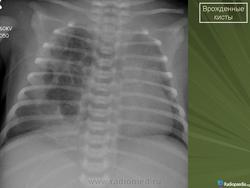

Кистозные поражения легких у детей

Нередко Rg-картина сходна с проявлениями воспалительного процесса ( в т.ч. туберкулезной этиологии)

Кистозная аденоматоидная мальформация тип I

• Кисты диаметром 2 – 10 см , выстланные мерцательным псевдослоистым цилиндрическим эпителием

• Между кистами могут располагаться тканевые элементы, напоминающие нормальные альвеолы

• Кисты связаны с бронхиальным деревом пораженной доли легкого